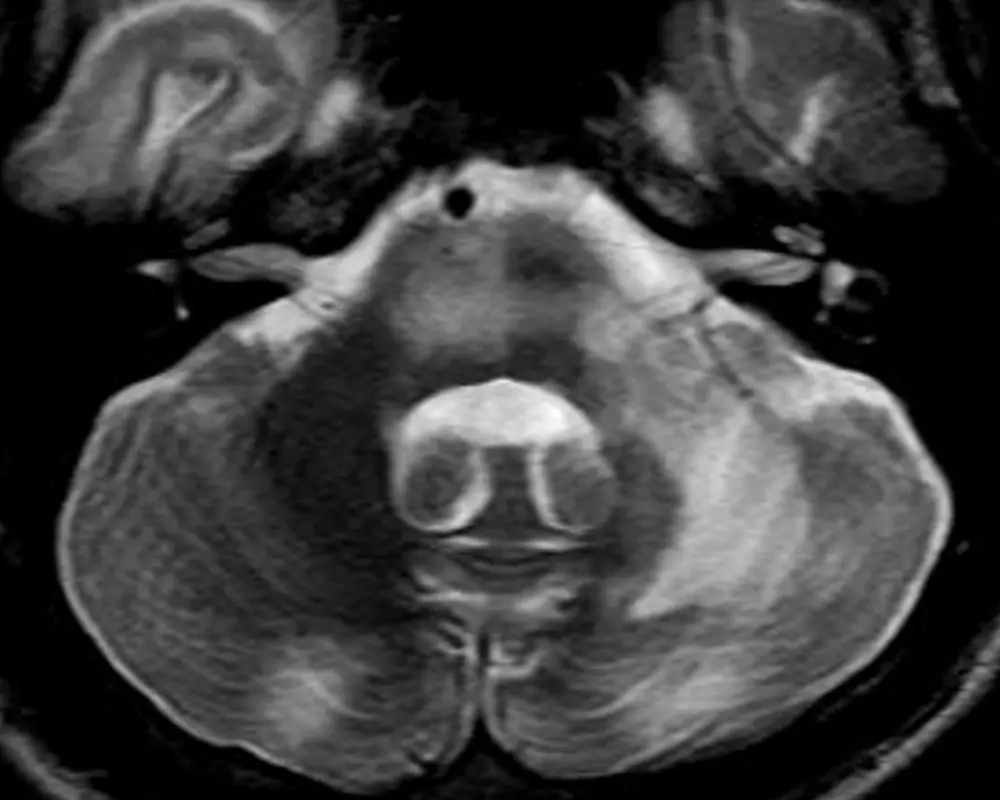

The flocculus is worth recognizing due to its tendency to mimic an extra-axial mass in the cerebellopontine angle (e.g. a vestibular schwannoma) on head CTs when asymmetrically prominent or dense, particularly in the axial plane. See Figure 5. and Figure 6.